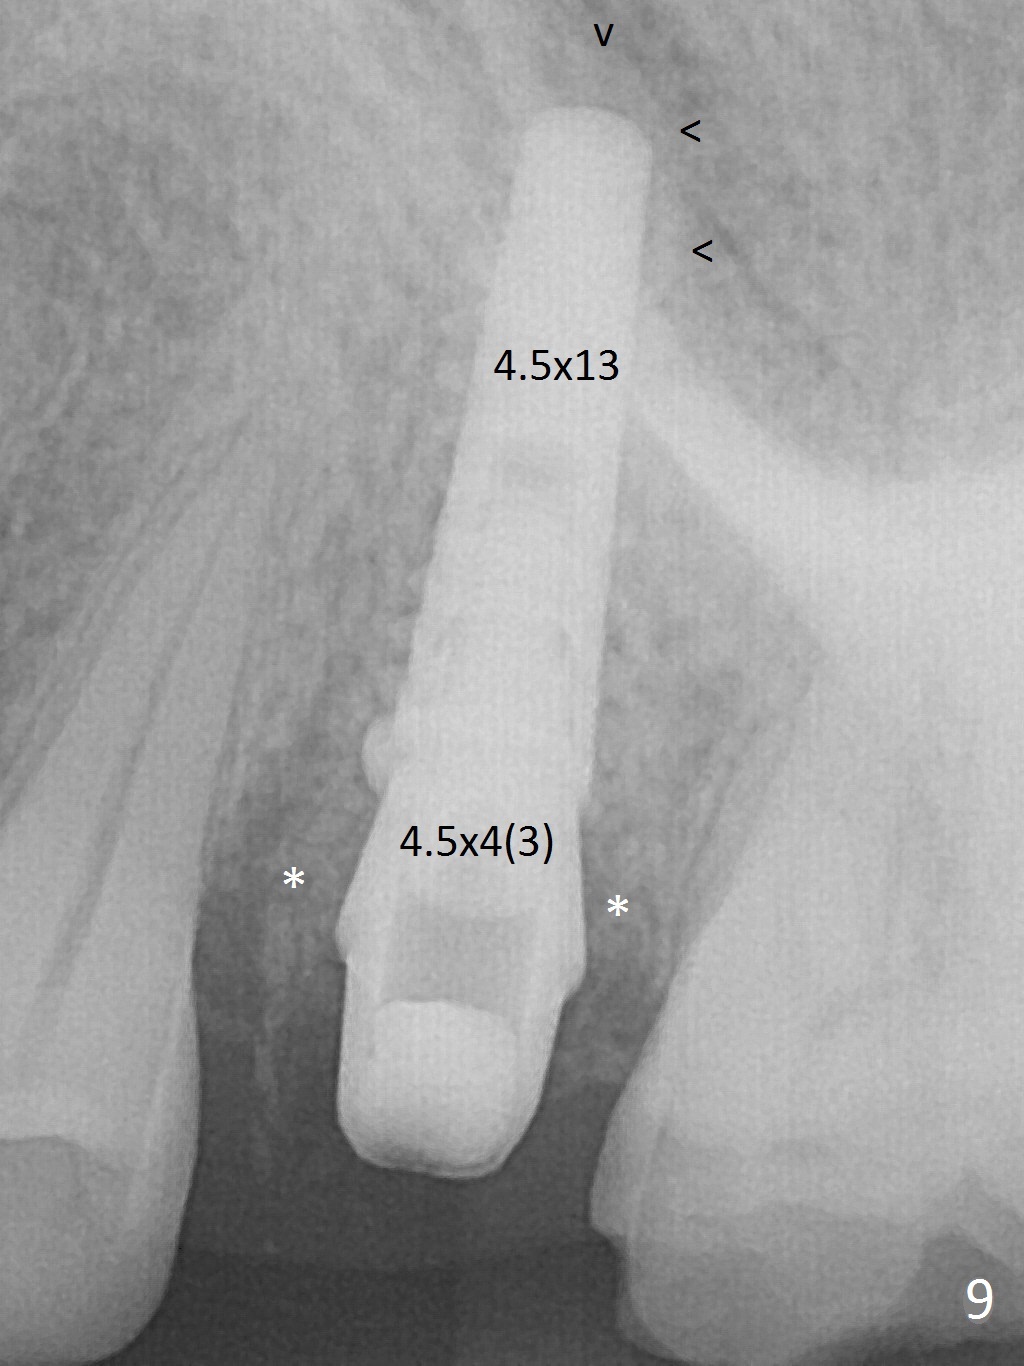

The buccal gingiva over the tooth #13 (Fig.1 white *) with crack (Fig.2 (mesial view of the extracted tooth)) is erythematous with deep buccal (B) pockets, which do not appear to extend the level of exostosis of the neighboring teeth (Fig.1 black *), i.e., coronal to the apical end of the crack with granulation tissue (Fig.2 *). Osteotomy is initiated with a 1.6 mm drill in the palatal aspect of the socket (Fig.3) so that an implant will be placed palatal (Fig.8,11) and there is enough buccal gap for bone graft (Fig.8 *). After withdrawal of 3.3 mm Magic Drill (trephine bur), the osteotomy (Fig.4 O) plug (red outline) is intentionally left in situ. When a 4x11 mm dummy implant is placed (Fig.5 (green outline), 6), the plug is compressed (Fig.5). With placement of a definitive implant (4.5x13 mm, Fig.7 (green), 9), the plug as well as the sinus floor (Fig.4 SF) is lifted (Fig.7 red curved line), 9 (arrowheads)). In brief the autogenous bone is used for sinus lift. There is no intra- or post-op nasal hemorrhage. With a small piece of gauze (Fig.8 G) in the implant well, allograft is placed in the buccal (mainly) and palatal gaps until the level of the implant plateau. Then a 4.5x4(3) mm abutment is placed (Fig.9-10 A). Next another piece of gauze is placed in the space corresponding to the abutment cuff (Fig.11 G) for fabrication of an immediate provisional (Fig.12 P). More bone graft is placed in the soft tissue zone (dual zone technique) after gauze removal and before provisional seating. With dual zone bone graft technique and provisional support, the soft tissue atrophy should be expected to be minimal (Fig.12 *). The zone of exostosis (more coronal) should be much less, since the bone density in the zone is high.